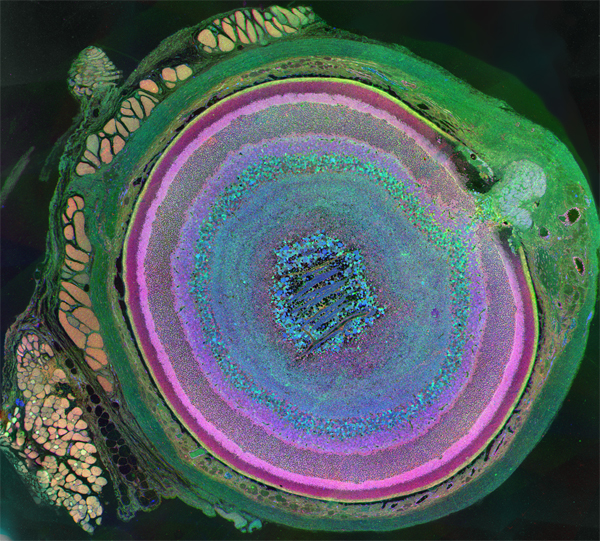

Cell Cycle Alterations in Chx10 Null and Chx10, p27Kip1 Double Null Retinal Progenitor Cells Reveal the Importance of Proliferation Rate in Promoting Retinal Development

The Chx10,p27Kip1 Double Null Retina Contains Cone Bipolar Cells, but Remains Severely Compromised in Visual Function

Bipolar Cell Blindness: Fast, Persistent Second Order Effects of Photoreceptor Degenerations